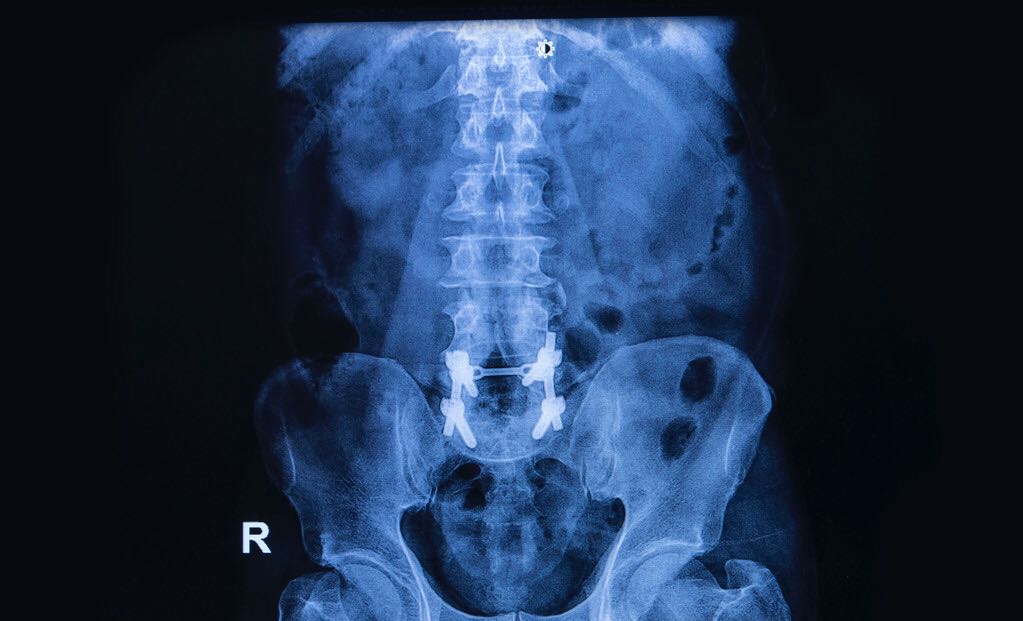

强直性脊柱炎是一种慢性的风湿病,发生病变的部位就在脊柱,病变特征就是脊柱强直。这种病一般在40多岁的男性群体比较常见。...[详细] 2024-10-08